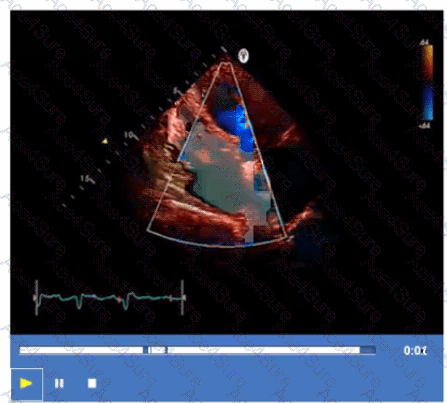

What is the incidental finding seen by color Doppler in this four-chamber view of a patient with left atrial enlargement?